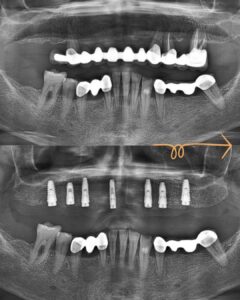

I assist my patients in my clinic in Istanbul/Turkey on Gum Diseases, Surgeries and Dental Implant Treatments.

In 2014, I took the Specialization Exam in Dentistry and was entitled to receive specialization training in the Department of Periodontology. During my residency training, I did many clinical and academic studies on gingival diseases and dental implant applications. In 2017, I defended my thesis titled “Low Level Laser Therapy Induces Increased Viability and Proliferation in Isolated Cancer Cells” and received the title of “Periodontist and Implantologist”.